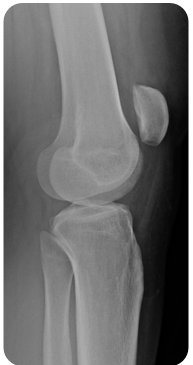

A 16-year-old boy presents to the ED with a knee injury sustained while competing in a gymnastics meet. His exam is shown above. What is the best next step in the treatment of this injury?

Provide pressure medially from the lateral aspect of the dislocated segment while simultaneously extending the knee